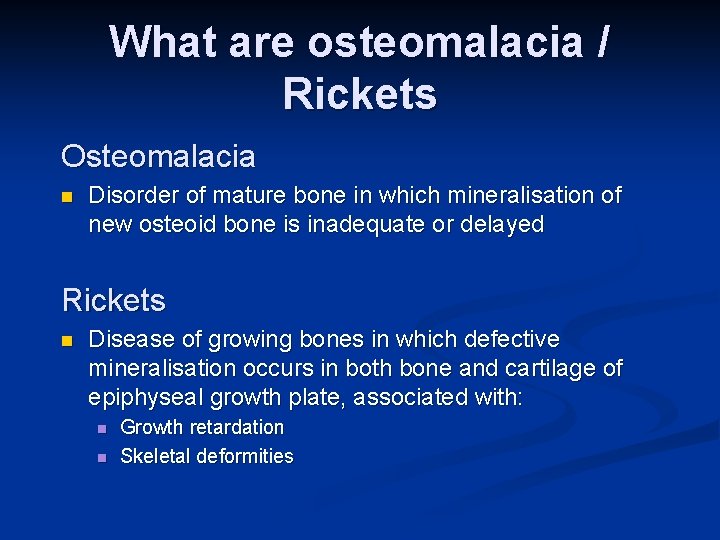

What are osteomalacia / Rickets Osteomalacia n Disorder of mature bone in which mineralisation of new osteoid bone is inadequate or delayed Rickets n Disease of growing bones in which defective mineralisation occurs in both bone and cartilage of epiphyseal growth plate, associated with: n n Growth retardation Skeletal deformities